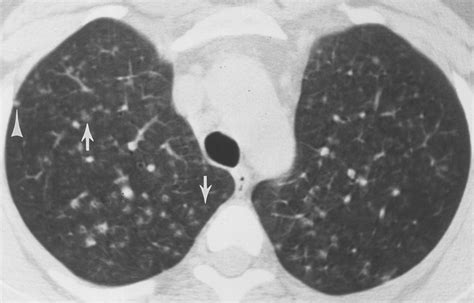

Diagnosis of Hot Tub Lung

Diagnosing hot tub lung involves a combination of medical history, physical examination, and diagnostic tests. Your healthcare provider may perform the following:

• Chest X-ray or CT scan to visualize lung abnormalities